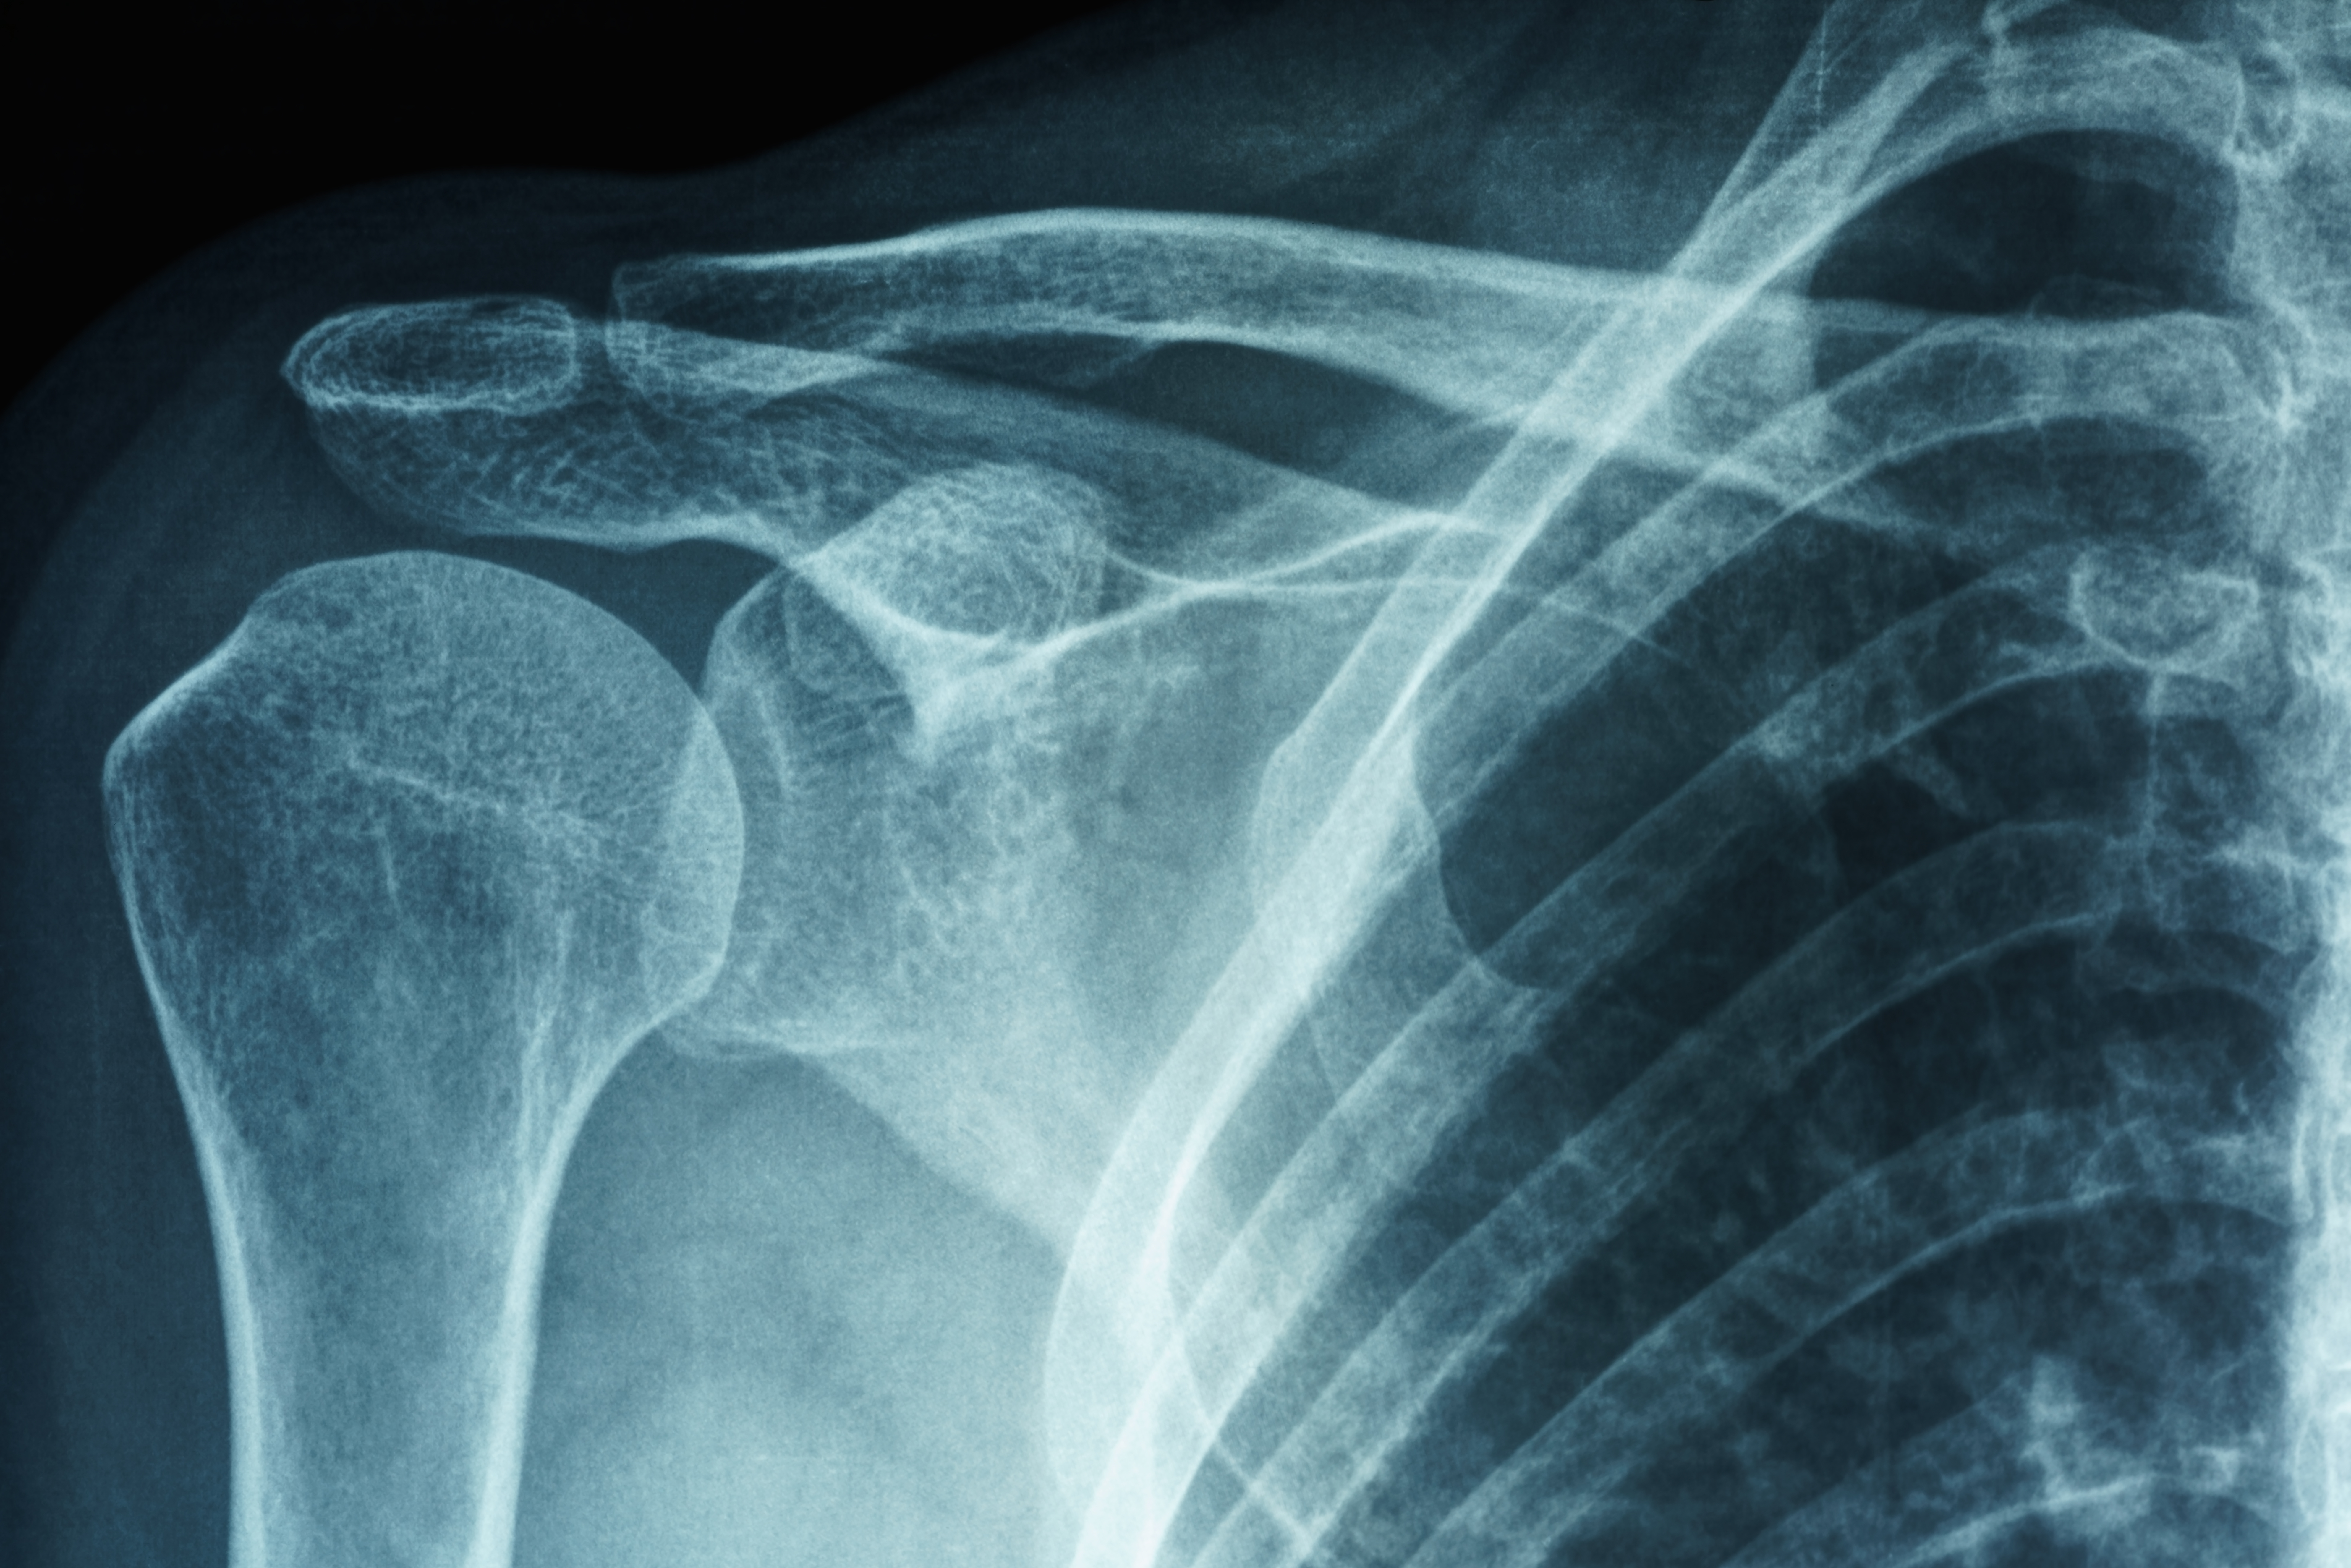

You will undergo a physical exam. Your OINJ shoulder doctor will test your active and passive range of motion to assess how well you can move your shoulder. Your OINJ shoulder doctor may also have you undergo an X-ray to see if there’s an underlying cause, such as shoulder arthritis or a broken bone.